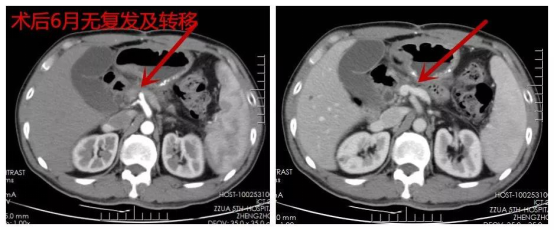

刘某术后来院复诊,1月复查CT肿瘤灭活(图2),3月复查CT肿瘤消除(图3),6月复查CT未见复发及转移(图4),1年复查CT部分胰腺组织萎缩、纤维化,肿瘤未见复发及转移(图5),2年复查CT(图6),病情稳定,未见肿瘤复发及转移。

▲ 图四